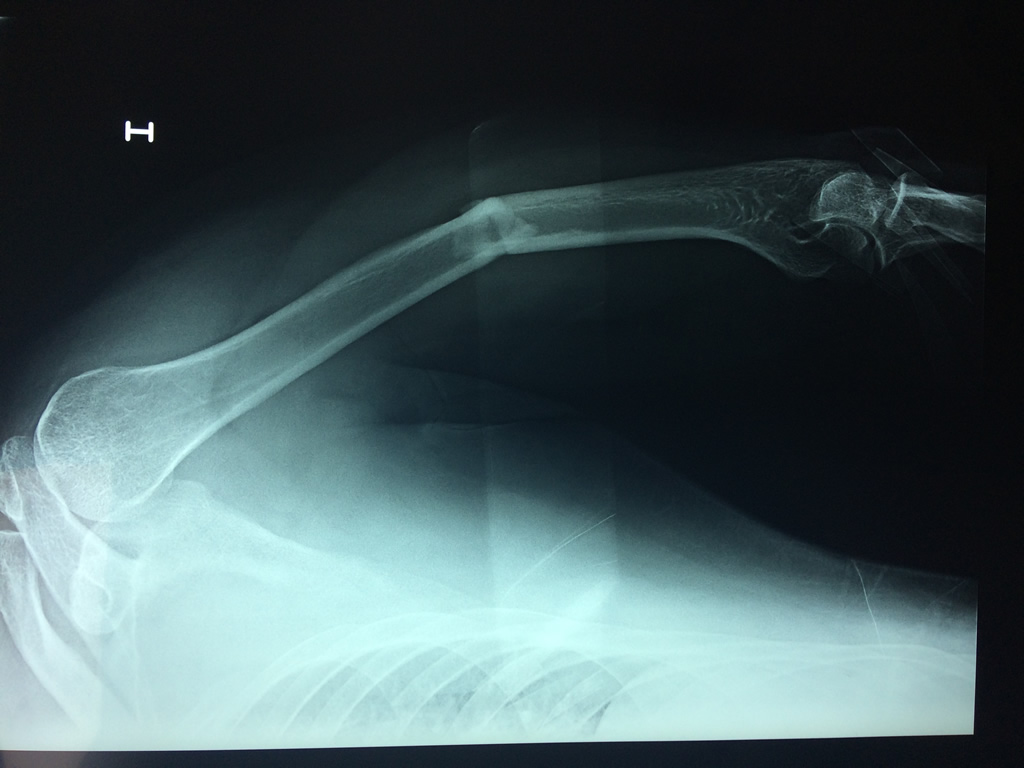

El Húmero (en latín, humerus) es el hueso más largo de las extremidades superiores en el ser humano. Forma parte del esqueleto apendicular superior y está ubicado en la región del brazo. ... El extremo proximal del húmero tiene la cabeza, cuellos quirúrgico y anatómico y tubérculos mayor y menor.